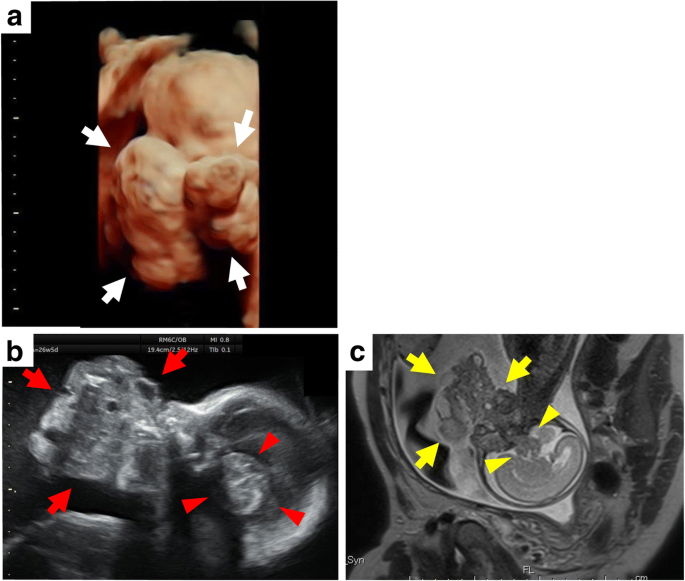

A 32-year-old woman, 3G2P (2 normal vaginal delivery, no abnormality) was referred to our hospital at 25 weeks of gestation for evaluation of a tumorous lesion located near the neck of the fetus, which was detected at gestational week 23. Prenatal three-dimensional ultrasonography performed at gestational week 25 showed a giant tumor around the neck and face (Fig. 1a). The spatial relationship between the tumor and the oral cavity was not confirmed; however, the possibility of an epignathus was strongly suspected. A prenatal ultrasound at gestational week 26 revealed a polyhydramnios, a giant tumor around the neck, and an intracranial tumorous lesion (Fig. 1b). Color Doppler ultrasonography showed arterial branches assumedly from the right internal carotid artery running into the giant tumor around the neck. Arterial branches from the right middle cerebral artery were suspected to be running into the intracranial lesion. These potential feeding arteries were of concern, because they could raise difficulties in the control of bleeding during an ex utero intrapartum treatment (EXIT) procedure. Magnetic resonance imaging (MRI) performed at gestational week 25 showed a giant tumor around the neck with heterogeneous iso-to-low signal density on T1-weighted images, and iso-to-high signal density on T2-weighted images. MRI also suggested a connection between the giant tumor and the intracranial lesion (Fig. 1c). An epignathus with intracranial extension was suspected. The possibility of preterm labor was a concern; therefore, supportive care with amnioreduction was to be provided until the fetus attained a certain weight and stage of organ development for performance of a cesarean delivery, at approximately 30 gestational weeks. At gestational week 27, after the amnioreduction was performed, a placental abruption occurred, and the fetus was delivered by emergency cesarean section. Chromosome analysis was not performed. The fetus was stillborn, and an autopsy was performed after 27 h, for pathological diagnosis and assessment of the intracranial lesion.

Ultrasonographic and MRI images. a Three-dimensional ultrasonographic image at gestational week 25 shows a giant tumor around the neck and face (white arrow), strongly suggesting an epignathus. b Ultrasonographic image at gestational week 26 shows a giant tumor around the neck (red arrow), and an intracranial tumorous lesion (red arrowhead). c MRI image at gestational week 25 suggests a connection between the giant tumor around the neck (yellow arrow) and the intracranial tumor (yellow arrowhead)